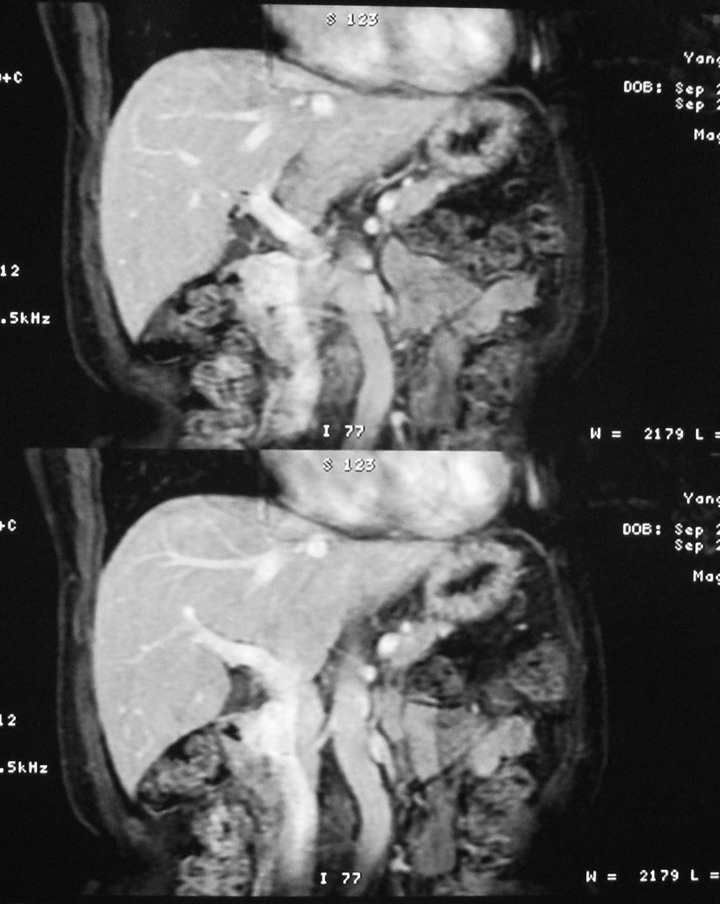

标题: MRI2066:腹膜后占位,请会诊,CT18531近期扫描图像

无明显不适,体检发现,

mri基本排除血管类肿瘤,明显强化说明极富血供,临床无症状,考虑胰岛细胞瘤可能大。

强化明显,并见有血管与之相连;考虑巨淋巴增生症.

极富血供的占位性病变,首先考虑良性,期待结果。